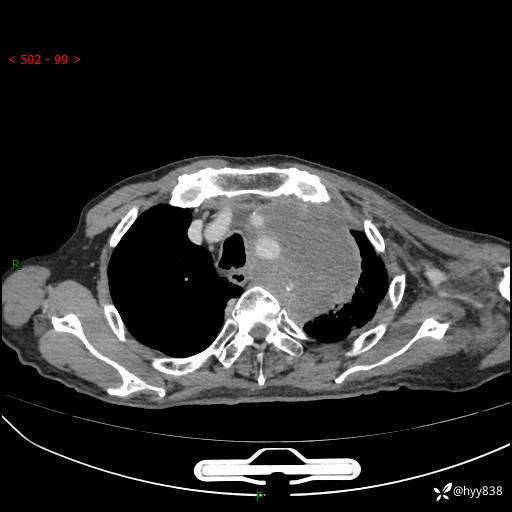

老年男性,气促5月,胸背痛2月。发现肺尖较大肿块,摧枯拉朽之势---结果公布~

现病史:患者于5月前饮酒后突发静息状态下气促不适,无胸闷、胸痛、发热、咳嗽、咳痰等不适,于当地第五人民医院及我院就诊,输液治疗后(具体不详)后气促稍缓解,遂出院后自行口服中草药治疗。近2月出现胸背痛,伴左上肢疼痛、乏力、感觉异常,稍有咳嗽、咳痰,咳黄痰、痰液粘稠,无咳血。为进一步诊治来我院。

胸部CT增强扫描(外院平扫)